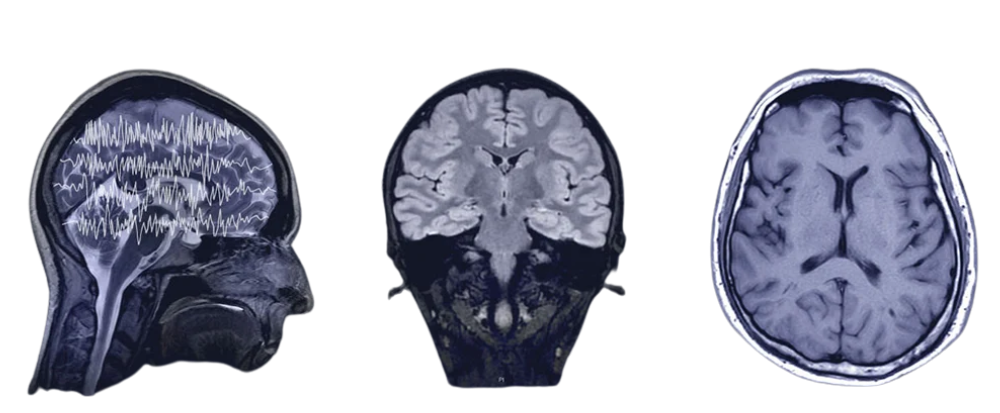

Memory loss is the inability to remember information, events, or experiences that were once known. It can be temporary or permanent and range from mild forgetfulness to severe conditions like dementia.

Early consultation with a neurologist is essential to identify the root cause of memory loss. A specialist, like Dr. Sachidananda Swain evaluates symptoms, performs cognitive and neurological tests, and creates a personalized treatment plan to improve memory and prevent further decline.

Consult Dr. Sachidananda Swain for advanced epilepsy Treatment